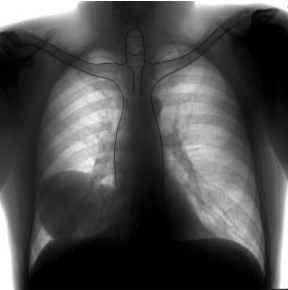

КТ картина эхинококковых кист зависит от стадии процесса. До прорыва в бронхи или плевральную полость киста имеет вид патологического образования овальной или неправильной формы. Последнее обычно связано с расположением ее рядом с более плотными анатомическими структурами. Контуры кисты четкие, ровные или волнистые. 'Структура чаще однородная. У части больных может быть выявлено частичное или полное обызветствление капсулы, что явля-етсявесьмахарактерным, но не патогномоничньш признаком эхинококкоза. Окружающая кисту легочная ткань не изменена. Количество кист может быть различным, но редко превышает 4-5. Применение КТ позволяет отличить кисту от мягко-тканного патологического образования округлой формы. При выявлении одиночной и, тем более, множественных кист в легком обязательным является ультразвуковое или КТ-исследование органов живота. Обнаружение кист в печени, селезенке, других органах живота, а также внеорган-ных кист является веским аргументом в пользу паразитарной природы изменений в легких. Кроме того, эти данные существенно влияют на последовательность оперативных вмешательств при эхинококкозе.

Важным объективным методом исследования является рентгенологический. Характерной рентгенологической картиной пеосложпенного эхинококка легкого является наличие овальной, четкой тени в легком па фоне неизмененной легочной ткани. При этом также классической рентгенологической картиной является наличие свободного реберно-диафратмального синуса (симптом Вотчала). При больших эхинококковых кистах, исходящих из нихжних долей, тень паразита сливается с тенью печени (рис. 52).

При рентгеноакопии иногда отмечается изменение формы и контуров кисты соответственно акту дыхания (симптом Немцова—Зекугдера), который также может иметь место при других кистозных образованиях: легких. Иная рентгенологическая картина наблюдается при осложненной стадии эхинококка легкого.

Наиболее типичным рентгенологическим симптомом вскрывшегося эхинококка является наличие газового пузыря с горизонтальным уровнем жидкости. Верхний контур газового пузыря имеет полукруглую или овальную четкую границу, образуемую стенкой фиброзной капсулы. При отсутствии выраженных воспалительных явлений в окружающей легочной ткани полоска затемнения бывает узкой и непосредственно переходит в неизмененную легочную ткань.

После прорыва кисты в бронх отмечается неровность контуров ее, а если эхинококковая жидкость полностью опорожнилась, удается увидеть кистозное образование в легком без четких контуров. При нагноении эхинококковой кисты наблюдается рентгенологическая картина абсцесса легкого (наличие горизонтального уровня жидкости, изменяющегося при перемене положения тела) (рис. 53). При прорыве кисты в плевральную полость рентгенологически устанавливается наличие воздуха и жидкости в плевральной полости, а также явление коллапса легкого и смещение средостения.

Несколько лет назад в больнице при плановой флюорографии у одного из пациентов мужского пола в нижнем легочном поле справа было обнаружено овальное затенение с четкими неровными контурами размерами 7,3-10,0 см. На момент исследования пациент жалобы не предъявлял, в ходе сбора эпидемиологического анамнеза контакты с источниками заражения эхинококком отрицал. Была назначена очная консультация онколога. Там были выписаны жалобы на редкий кашель, который сам пациент связывает с курением. Было принято решение о динамическом наблюдении пациента.

При прохождении флюорографии год спустя без видимой динамики, еще год спустя - увеличение тени до 10 см, по сравнению с предыдущими годами прослеживалась отрицательная динамика. Было рекомендовано КТ органов грудной клетки и повторная консультация онкологов.

На консилиуме принято решение об оперативном удалении образования, в ходе гистологического исследования была подтверждения его природа – эхинококковая киста. В настоящее время пациент чувствует себя удовлетворительно, жалоб не предъявляет. Снимков из послеоперационного периода, к сожалению, нет.